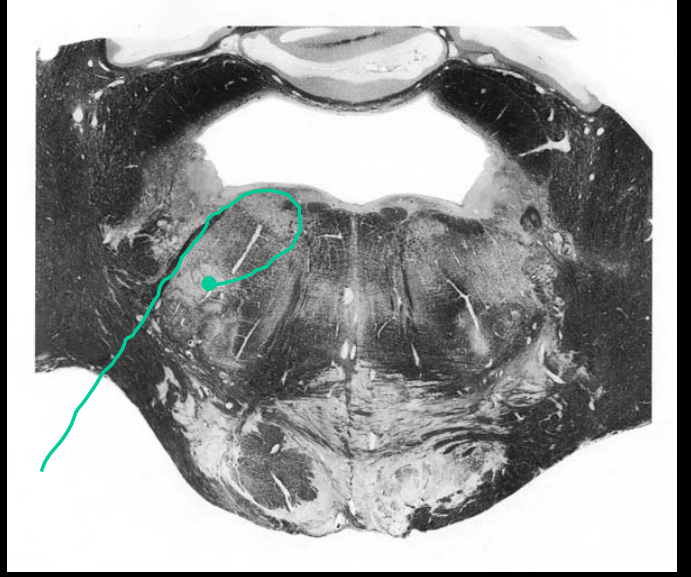

Solitary nucleus in the rostral medulla; the origin of the special (visceral) sensory fibers of CN VII (gustatory), which innervate the anterior 2/3 of the tongue.

Facial motor nucleus, origin of the branchial motor (special visceral) fibers of CN VII that innervate all the muscles of facial expression, stapedius m., stylohyoid m., and posterior belly of the digastric m.